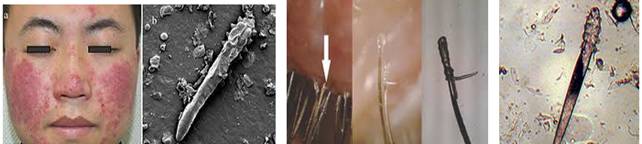

Hình 1